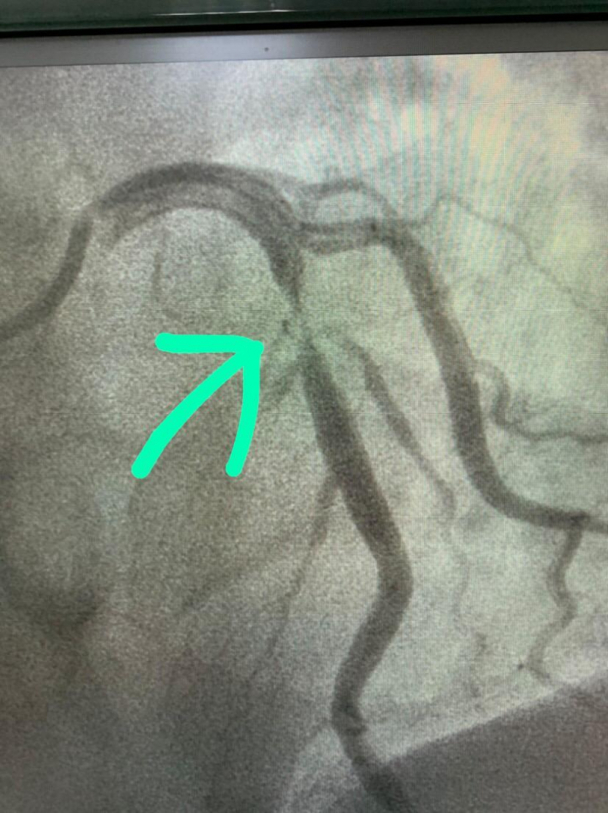

Vamos começar!”. Não tenho como narrar toda a conversa a partir daquele momento, só me recordo dela falando coisas como “seu Marco, respire fundo!”, “seu Marco, agora respire bem devagar, bem devagar mesmo seu Marco!”, “seu Marco, sente alguma coisa?”; eu, “sim, doutora, está doendo um pouco”, “normal, seu Marco, estou inflando o balão”... Passou um minuto, “seu Marco, ainda sente?”; eu, “nada doutora, nada mesmo”; ela, “já inflei, o stent foi colocado com sucesso. Conseguimos, seu Marco, conseguimos!”.

Novamente me fez lembrar do Haiti, quando conquistávamos os pontos de domínio dos criminosos. Aquela equipe tinha cumprido sua missão, tinha conquistado o campeonato, o campeonato daquele dia. Sai daquela sala sob um surpreendente brado da doutora, “faca na caveira”, no que eu respondi com extrema felicidade, “...e molinha na artéria!”. Todos riram. Pode parecer meio piegas, mas foi o dia mais feliz do meu coração.

Depois

Depois / arquivo Pessoal